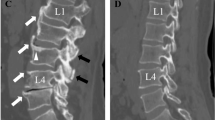

The region of interest (ROI) on axial non-contrast CT image of the L1 vertebra was manually labeled by two radiologists who were blinded to the clinicopathological details of patients. The ROI was drawn on the mid-vertebral level of the L1 vertebral body to avoid cortical bone and the basivertebral vein (Supplementary Fig. S1), as previously described [18]. Quantitative radiomic features were then extracted from the ROIs using the PyRadiomics v3.0.1 package [19]. All steps of ROI labeling were repeated one month later by the junior radiologist to test the intra-observer variability [20].

Supplementary file1 (TIFF 569 kb)—Supplementary Fig. S1 The axial unenhanced CT image of the L1 vertebra was used for image segmentation. The region of interest (ROI; yellow circle) was drawn on the mid-vertebral level of the L1 vertebral body avoiding cortical bone and basivertebral vein.